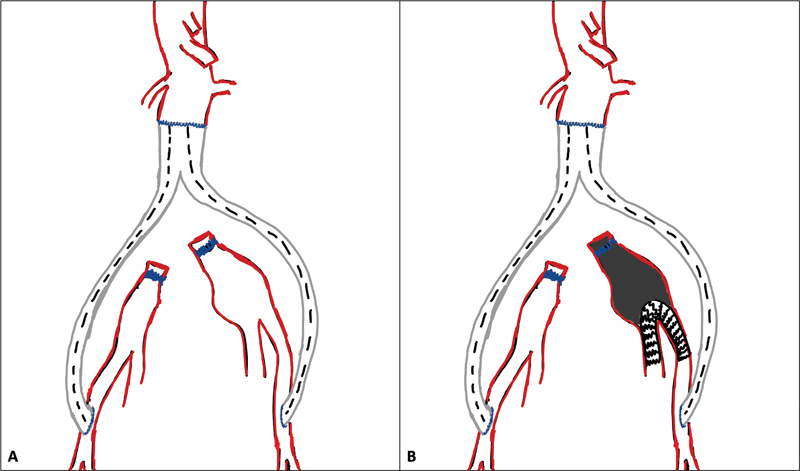

Abstract Image